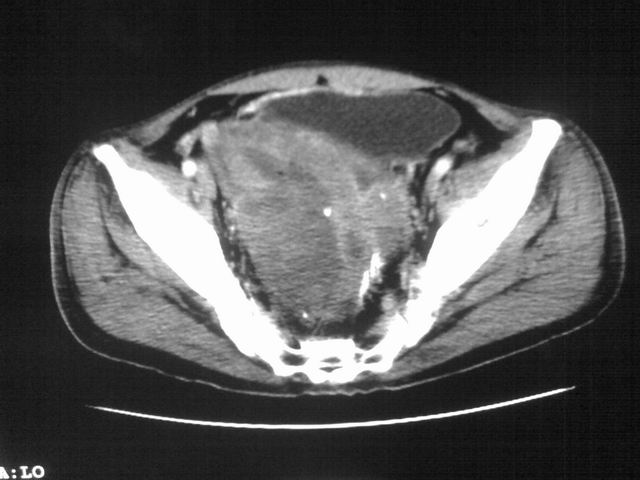

患者m 56岁,盆腔及下腹部胀痛半年,加重1月余,消瘦\中重度贫血.(附:平扫时直肠的高信号为,残留的钡剂).补一下病史:胃镜及纤维结肠镜均无明显异常.

膀胱后方及直肠前方见巨大混杂密度影,与前列腺相连且向膀胱内突入,精囊腺显示不清;考虑前列腺癌侵犯精囊、膀胱。

膀胱及直肠间有不规侧的软组织密度影,内密度不均匀。其内有坏死囊变,前列腺及精囊腺,膀胱后壁受浸。结合病史考虑腹膜后肉瘤可能性大。